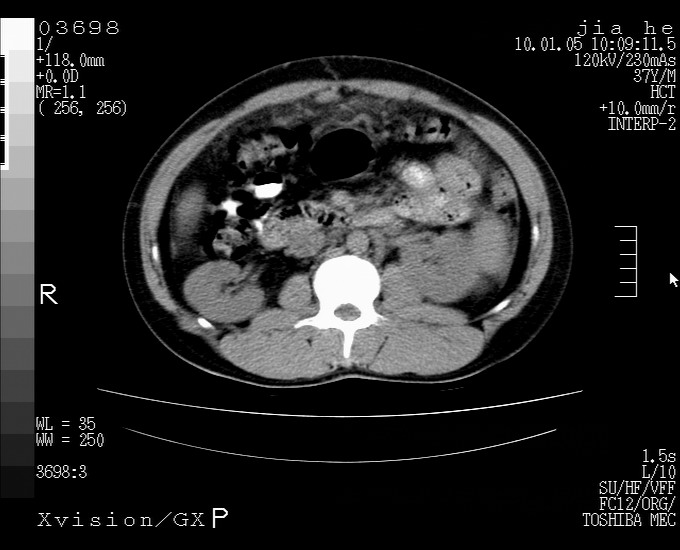

标题: CT23988:男,40岁,B超提示腹部肿物,请各位老师给看看。 [打印本页]

标题: CT23988:男,40岁,B超提示腹部肿物,请各位老师给看看。

1.该患者有腹部手术史

2.脾大,肠系膜密度增高,有多发索条影,胰腺边缘毛糙,腹膜增厚,推测有肝硬化,门脉高压,腹膜炎和/或胰腺炎

3.肝左叶巨大站位,并腹腔淋巴结肿大,肝癌或肝间叶来源恶性肿瘤,也不排除大网膜间质瘤侵及肝左叶

建议:增强或磁共振